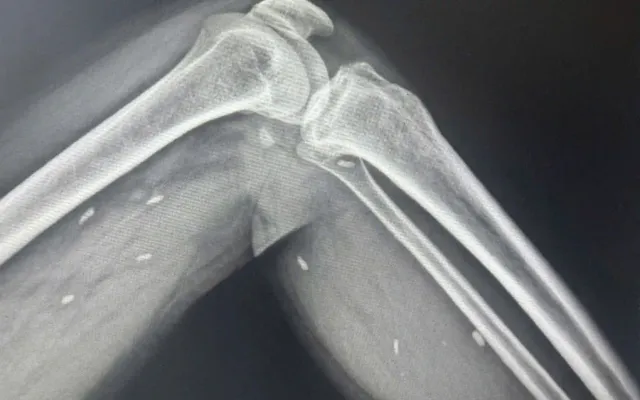

Qua chụp X-quang, các bác sĩ phát hiện nhiều kén sán kích thước như hạt gạo nằm rải rác ở các mô vùng đùi và cẳng chân bệnh nhân. Khi khai thác tiền sử dịch tễ, người bệnh cho biết có thói quen ăn rau sống. Sau đó, bệnh nhân đã được chuyển lên tuyến trên để tiếp tục điều trị.